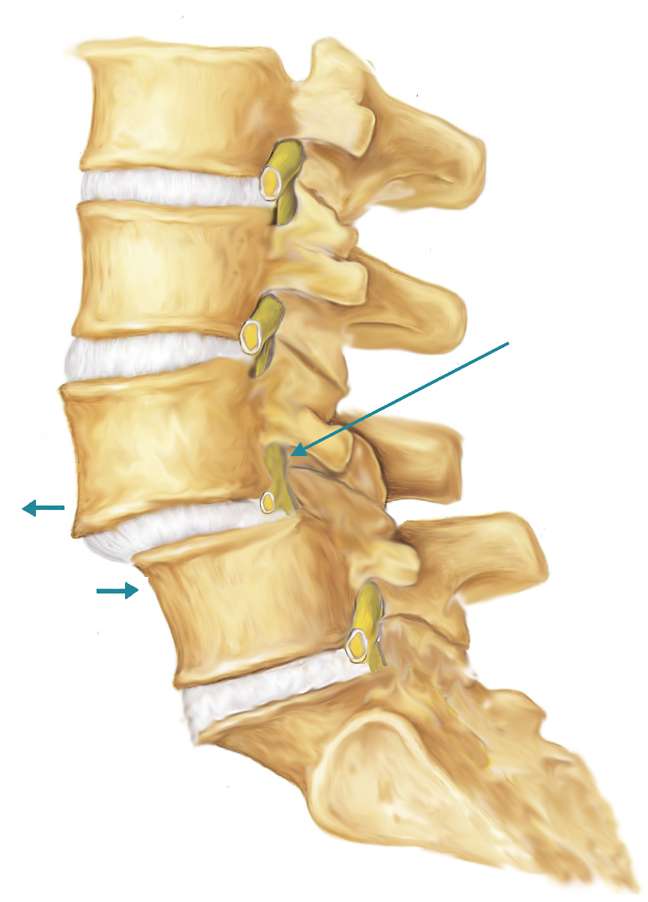

Позвонок Th10: анатомия и фото медицинских иллюстраций